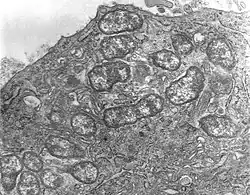

Orientia is a genus of bacteria in family Rickettsiaceae. They are obligate intracellular, gram-negative bacteria found in insects and mammals. They are spread through the bites or feces of infected insects.